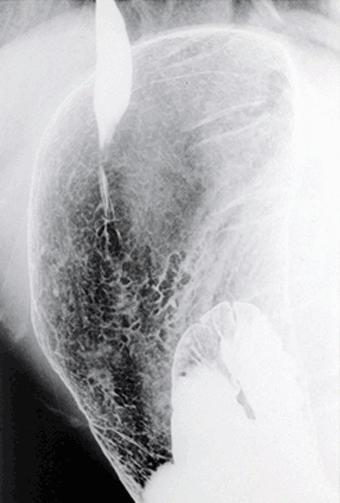

광범위(전정부~ 분문직하)하게 나타난 IIb+IIc형 조기위암

0형(표재형)/IIb형(IIb+IIc)

40이상

m